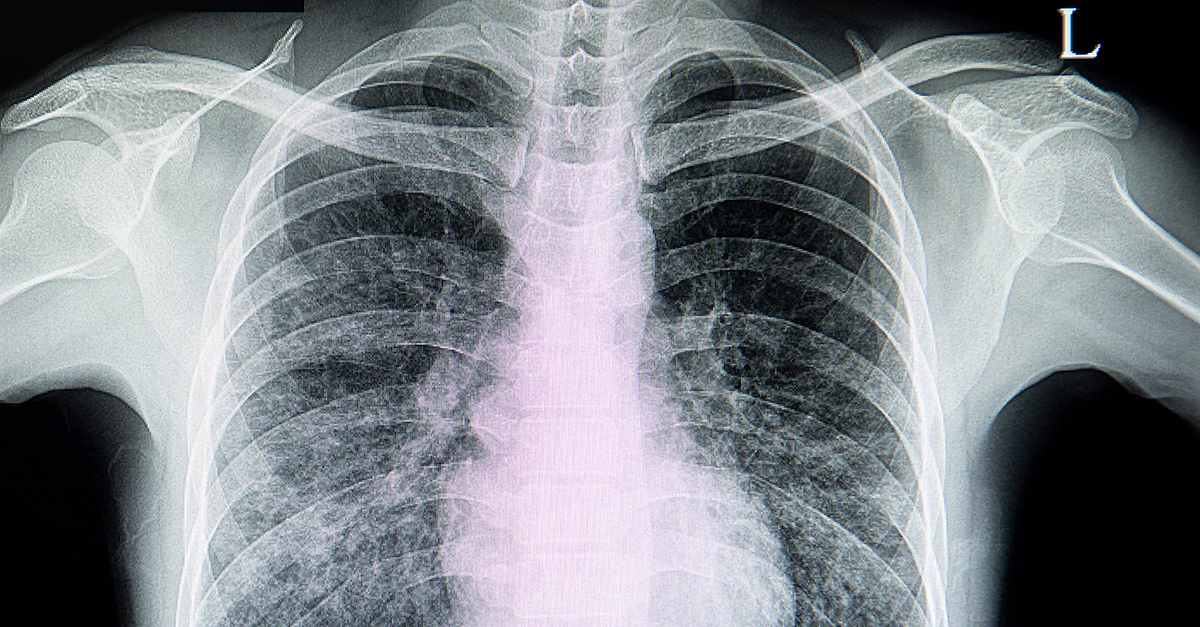

Once the pulmonologist has a reason to suspect interstitial lung disease, they will generally order a high-resolution CT scan of the lungs, which helps diagnose and detect patterns of lung changes that could be helpful in categorizing the type of disease.